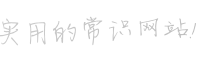

2017年9月29日,從CT影像看到右腎情況更為嚴重。為減緩腫瘤增長的速度,專家進行商議后,最終決定由牛立志教授主刀為安圖叔叔進行了右腎腫瘤冷凍消融術。手術開始后,牛立志教授在CT和超聲引導下,同時使用兩根冷凍針固定病灶,精準滅活腫瘤;術后很成功無不良反應。術后一周進行第二次雙腎腫瘤冷凍消融術。安圖叔叔兒子笑道:“當時真的很緊張,醫生勸慰我無須擔心,都交給他們,我們都很清楚知道父親的病情,真的很感謝也很慶幸我父親遇到復大的醫護人員,免受開刀之痛。住院期間醫護人員很盡心盡力的照顧父親,手術的成功離不開他們的辛勞付出。”

冷凍治療手術中